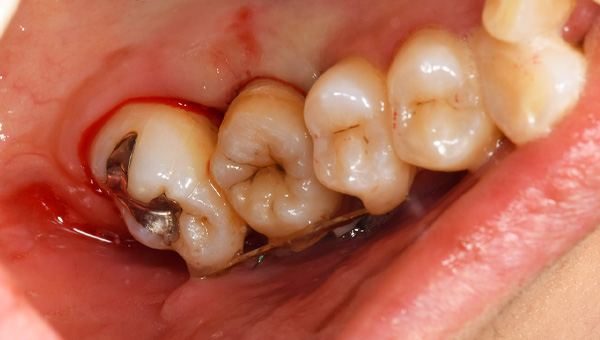

歯が大きく欠けた

説明:

右上の歯が大きく欠けています。黒く虫歯になっているのがわかります。移植を計画しましたので、歯ぐきがしっかり治癒するのを(1ヶ月)待ちました。